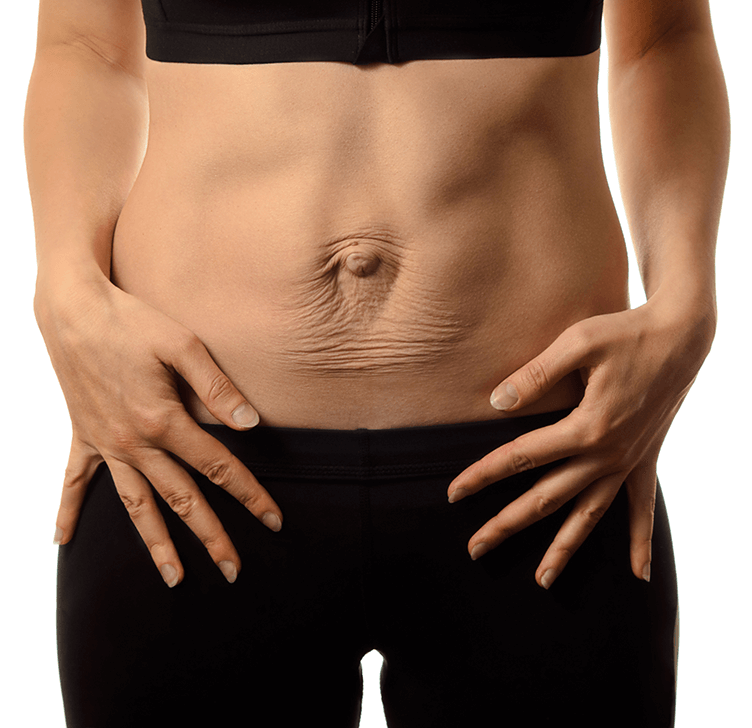

Understanding Cystocele and Rectocele: Causes, Symptoms, and Treatment Options Pelvic floor disorders such as cystocele…